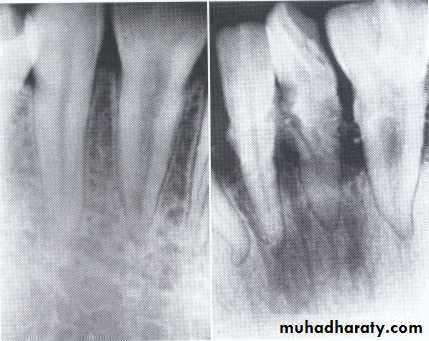

Radiographically:

Bulbous crownsCervical constriction

Thin roots

Early obliteration of roots canals & pulp chambers.

Radiographically (Type I& II ):

partial or total obliteration of pulp chambers & root canals by continued formation of dentin.

roots may be short & blunted.

Normal cementum, periodontal membrane & bone .